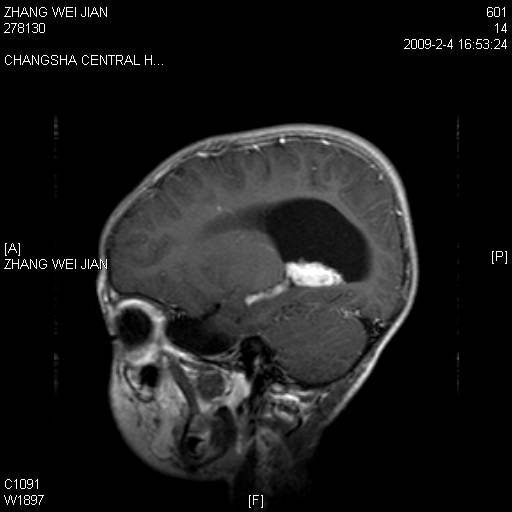

以下是引用guanaishengming在2009-2-6 22:51:00的发言:[br]脉络丛乳头状瘤

以下是引用随光逐影在2009-2-7 8:30:00的发言:[br]考虑双侧脑室脉络丛乳头状瘤并脑积水。

以下是引用同在2009-2-7 15:13:00的发言:[br]脉络丛乳头状瘤并脑积水。